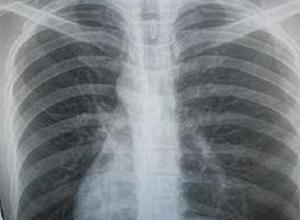

常引起本症狀的疾病有慢性支氣管炎、支氣管擴張、風心病、先心病、塵肺、癌性淋巴管炎等呼吸和心律增快、肺部羅音、肺動脈瓣第二心音亢進。胸片呈現肺部斑片狀

肺紋理增粗檢查

(1)支氣管性肺紋理增多:表現為肺紋理粗細不勻,其中常夾雜變形紋理和小蜂窩影,常見於慢性支氣管炎、支氣管擴張等。(2)血管性肺紋理增多:肺紋理粗大,從肺門向肺內保持血管走行的特性,常伴有心臟增大的表現,主要見於風心病、先心病等。(3)淋巴性肺紋理增多:肺紋理在兩肺內呈纖細的網狀,常見於塵肺、癌性淋巴管炎等。(4)吸菸性肺紋理增多:顯示雙肺紋理增多,但走行正常,主要是由於長期吸菸引起的炭末沉著症所致。(5)生理性肺紋理增多:主要見於老年人和肥胖者。前者是由於老年人肺間質相對較豐富,從而在X線胸片上顯示肺紋理增多;後者是由於受檢者體質肥胖,皮下脂肪增多,導致X線吸收增加,從而引起胸片上肺紋理增多的假象。鑑別診斷